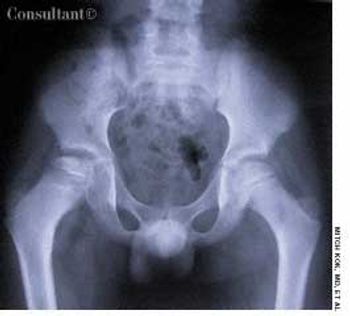

Gonococcal infection is the leading cause of bacterial arthritis in adults.